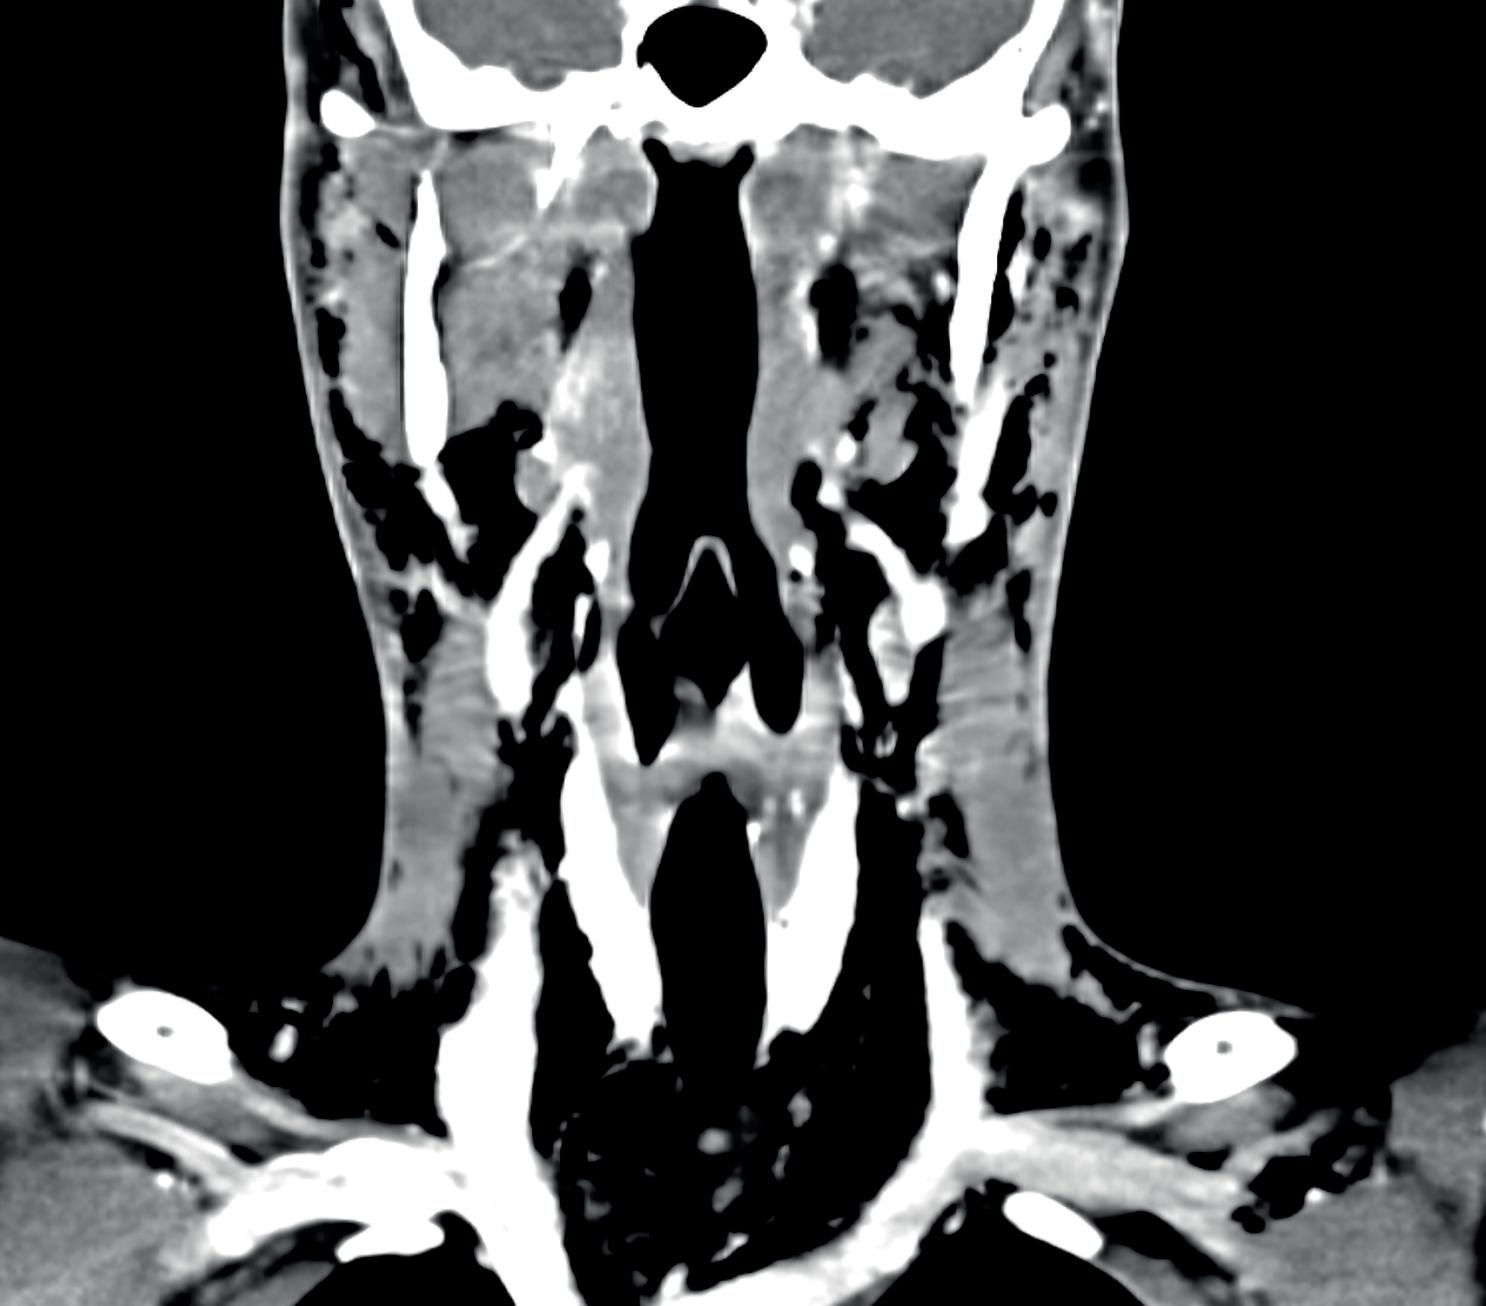

Kjære leser, jeg håper ikke forsidebildet skremte deg, men snarere pirret nysgjerrigheten. Temaet denne gangen er inflammatorisk tarmsykdom (IBD), og bildet viser en typisk manifestasjon: fistulerende Crohns sykdom. I denne utgaven finner du interessante og spennende artikler om alt fra prehabilitering av pasienter med IBD til avanserte medisinske og kirurgiske behandlingsmetoder.

Behandlingen av IBD har blitt betydelig bedret gjennom de siste årene med tilkomst av flere nye og effektive medikamenter, og behovet for stor og repetert kirurgi har avtatt betraktelig. Likevel er det fortsatt behov for et tett samarbeid mellom gastroenterolog og gastrokirurg da mange pasienter fortsatt vil trenge kirurgisk intervensjon. Tidsaspektene ved behandlingen - både medikamentell behandling, prehabilitering og kirurgi - kan ha stor betydning for det videre forløpet, både for aktuell sykdomshendelse, men også gjennom et helt liv med kronisk tarmlidelse. Langvarig inflammasjon og ernæringssvikt kan føre til at rekonstruktiv kirurgi med anastomoser eventuelt ikke kan gjennomføres, og infeksiøse komplikasjoner med fistler kan gjøre kirurgien mer omfattende og inngripende dersom sykdommen får utvikle seg i ventetid på behandling. IBD-kirurgi, og spesielt ved Crohn, er beheftet med økt komplikasjonsrisiko. En ekstra årvåkenhet når det gjelder preoperativ vurdering av sykdomsaktivitet, ernæringsstatus og øvrig klinisk status er spesielt viktig.